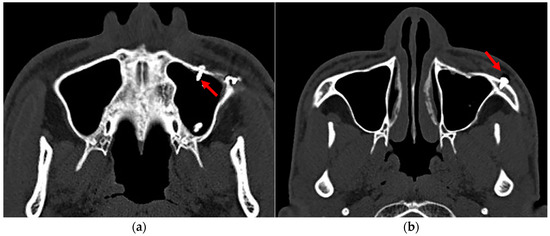

3. Results

4. Discussion